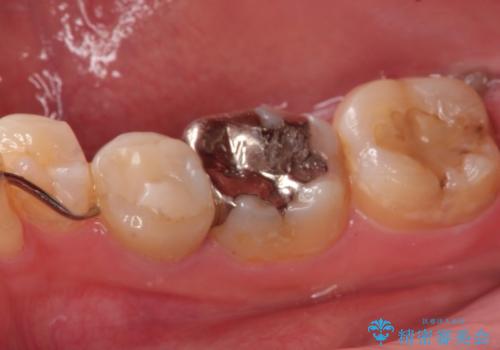

- 下顎の銀歯と、かぶせ物が外れたままになっている歯の治療を主訴に来院されました。

左下の奥歯はかぶせ物が外れて、土台が露出している状態でした。